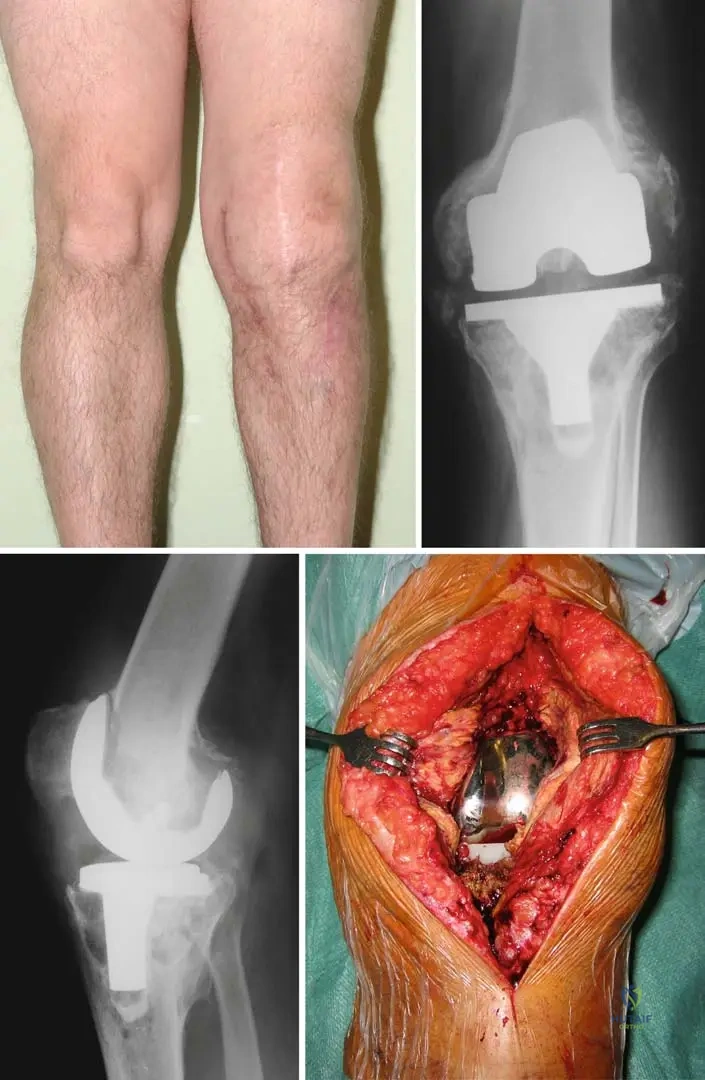

A 52-year-old male with a 20-year history of heavy alcohol consumption presents with severe right hip pain, significantly limiting his ambulation. He reports progressive pain over the past year. Physical examination shows a Trendelenburg gait, markedly restricted and painful range of motion in all planes of the right hip. Radiographs reveal flattening and sclerosis of the right femoral head with subchondral collapse and joint space narrowing.

View Answer & Explanation

Correct Answer: C

Rationale: The radiographic findings of femoral head collapse (subchondral collapse) and joint space narrowing in the setting of avascular necrosis (AVN) indicate advanced disease (e.g., Ficat Stage III or IV). At this stage, joint-preserving procedures like core decompression or osteotomy are generally not effective. Total hip arthroplasty is the most appropriate surgical treatment for advanced AVN with femoral head collapse and significant functional impairment. NSAIDs and activity modification are palliative and insufficient for advanced disease. Arthrodesis is rarely performed for hip AVN due to its significant functional limitations.

Question 41

A 60-year-old male with a long history of alcohol abuse presents with severe, debilitating bilateral hip pain. Radiographs show Ficat Stage IV avascular necrosis of both femoral heads with significant collapse, joint space narrowing, and secondary degenerative changes. He has failed conservative management. What is the most appropriate surgical treatment?

Rationale: For late-stage avascular necrosis (Ficat Stage III or IV) with femoral head collapse, significant pain, and secondary degenerative changes, total hip arthroplasty (THA) is the most effective treatment to relieve pain and restore function. Core decompression and osteotomy are indicated for earlier stages before collapse. Arthrodesis is a salvage procedure that sacrifices motion for pain relief and stability, generally not preferred for bilateral disease or in older patients. Non-weight-bearing and pain management are conservative measures that have failed in this scenario.